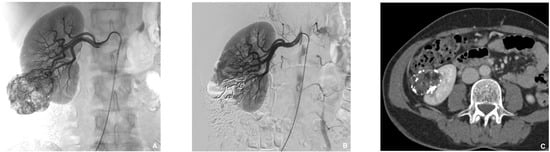

Figure 6. Prophylactic selective embolization of a large angiomyolipoma of the right kidney. (A) Angiography shows two feeding arteries to the angiomylipoma which is hypervascular. (B) Final control after selective and fast embolization of the two arterial branches with a Glubran®2/Lipiodol® mixture of a 1:6 ratio. (C) Computed tomography scan at day 14 showing lipiodol uptake by the angiomyolipoma which is totally devascularized.

Jcm 10 04320 g006